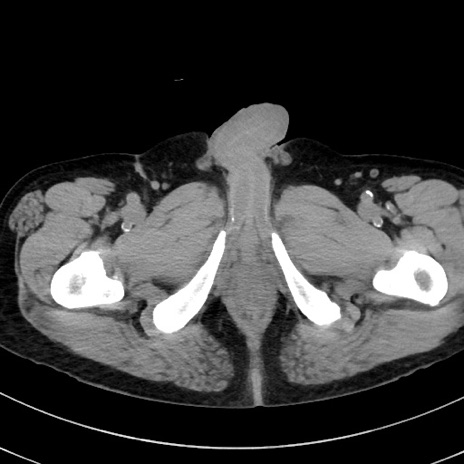

冠状断像